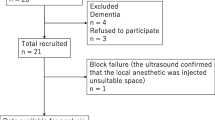

From October 2019 to August 2020, a total of 65 patients were assessed for eligibility to participate in this study. Two patients failed to provide the written informed consent. Two patients were excluded by exclusion criteria. Finally, 61 patients were included.

As determined by pinprick test, successful block was achieved in 54 patients. There were no differences in terms of demographic characteristics between patients with successful block and patients with failed block (Table 1).